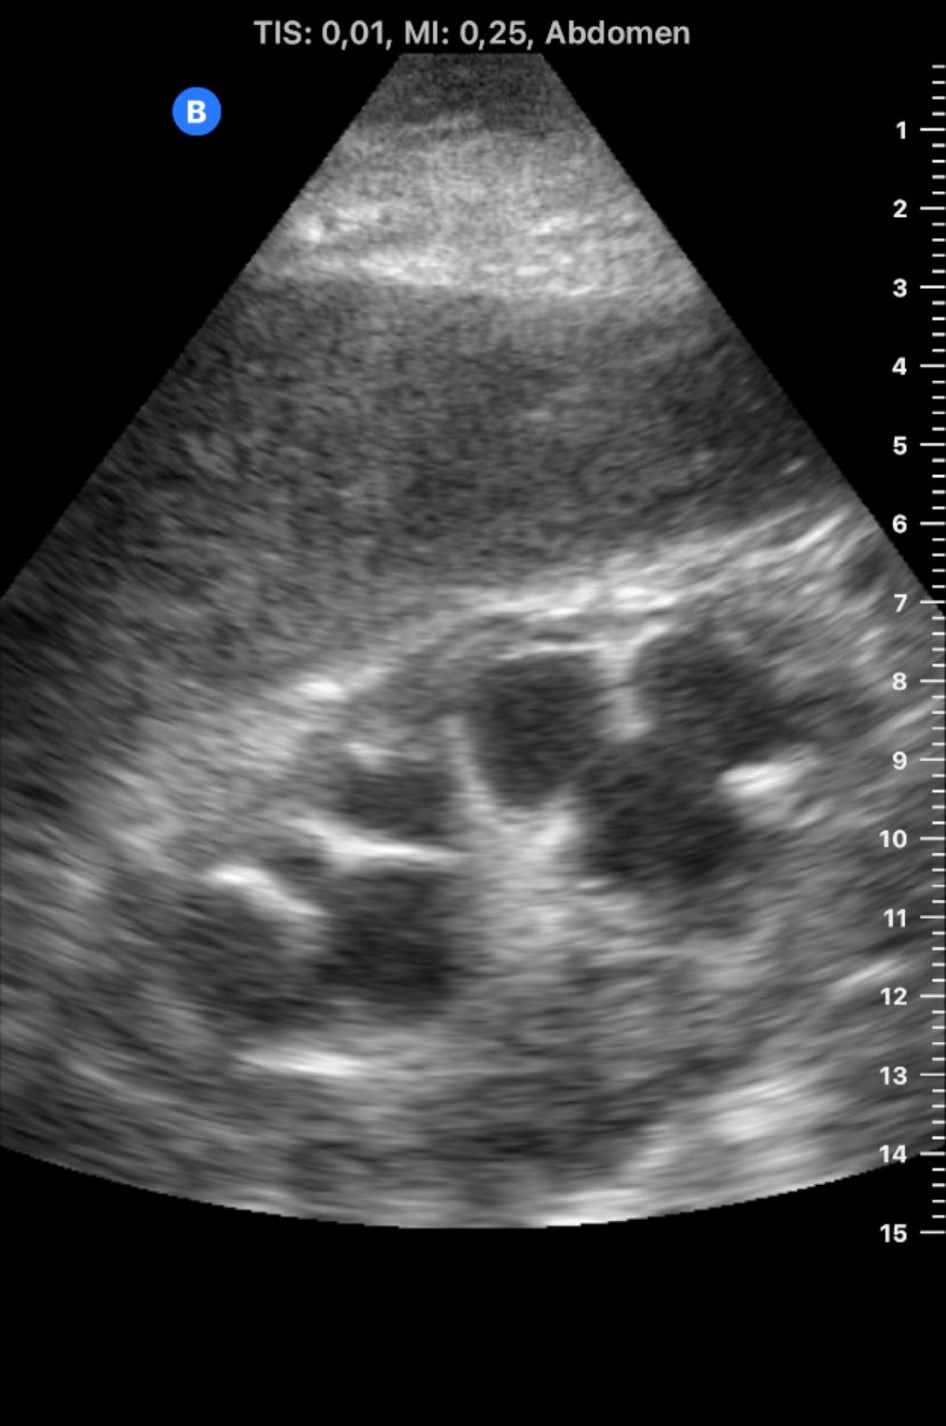

Se lleva a cabo una ecografía abdominal a pie de cama que evidencia ambos riñones de tamaño y localización normal. Relación corticomedular no conservada de riñón derecho debido a hidronefrosis grado IV, sin litiasis visible.